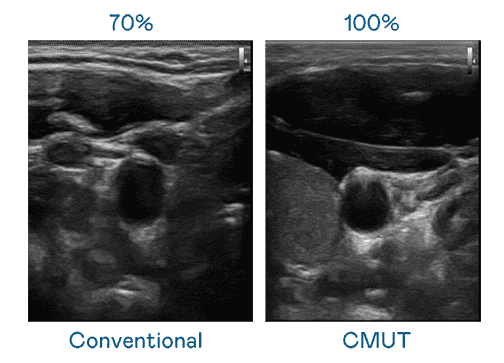

CMUT 技术是一种用电容式微机电元件来产生超音波讯号的技术。。。与传统 PZT 压电式技术相比,,,CMUT 频宽增加 30%,,,更宽频的超音波讯号让影像解析度大幅提升,,,是实现高影像品质医疗超音波扫描、、促进精准医疗发展的关键技术。。。

大频宽带来超清晰影像

超音波影像的解析度高低,,,首先取决于探头能发出的讯号频宽。。Wepay CMUT 可提供高清晰的超音波讯号,,提供高频宽、、、、高灵敏度、、、、影像纹理细节更高的超音波影像,,,,协助医护人员缩短影像判读时间及利用精准的医疗影像进行诊断。。。